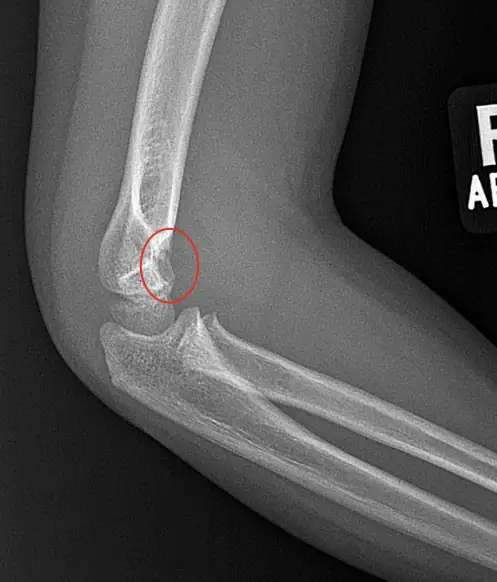

The correct diagnosis is a supracondylar fracture. The x-ray shows elevated distal humeral fat pads and a cortical lucency in the distal humerus, both supporting the diagnosis. Supracondylar fractures are the most common elbow fracture in pediatric patients. These injuries are typically seen in younger children – 90% are seen in children younger than 10 years of age. They are almost always due to accidental trauma such as falling on an extended elbow from a moderate height such as a bed or monkey bars. Rarely are they seen after a fall on a flexed elbow. Supracondylar fractures are graded as Gartland Types I – IV. Type I fractures are nondisplaced; Type II – IV are displaced fractures and require urgent orthopedic consultation and often surgical management. Higher grade fractures carry higher risks for complications including compartment syndrome, neurologic deficits and malunion deformities.

- On X-ray images, look for cortical irregularly or obvious fracture above the humeral condyles

- A posterior fat pad sign or sail sign indicates joint effusion and may be the only clue in the case of a non-displaced fracture